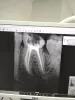

До конца ли верхушки корня запломбированы каналы зуба?

Перелечивала каналы, доктор знал, что до его лечения каналы были не до конца запломбированные. Я посмотрела на снимок, и спросила, здесь правильно ли запломбированы каналы. Он мне ответил, что каналы идеально запломбированы. Просто на снимке есть изменения в периодонтите (поэтому и перелечивала каналы, так как они были не до конца запломбированные, и начал развиваться периодонтит). Поэтому для меня было важно, чтобы каналы пролечили правильно. На данный момент зуб побаливает, и дискомфортно при накусывании. Сегодня только четвертый день после лечения, наверное, так и должно быть. И я вот сомневаюсь. Понимаю, что есть разные протоколы лечения, но мне кажется, что каналы плохо запломбированы.

Правильно ли запломбировали каналы?

Канал дистального корня пройден до верхушки. Каналы медиального корня не до верхушки пройдены. Судить о качестве перелечивания сложно, так как здесь важно учитывать медикаментозную обработку канала свойства организма в целом.